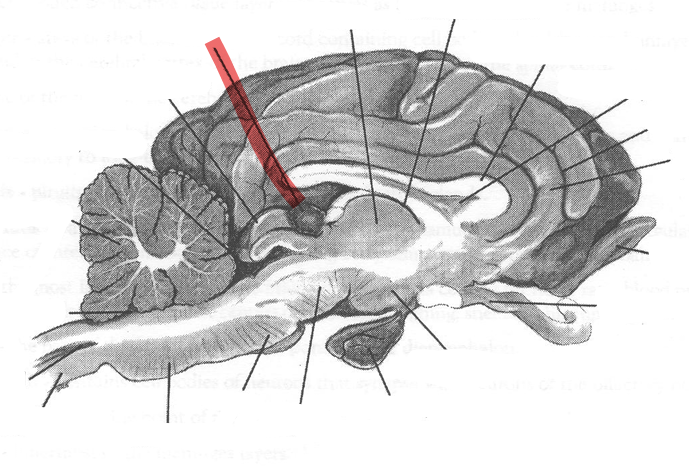

Identify highlighted arrow

Midbrain